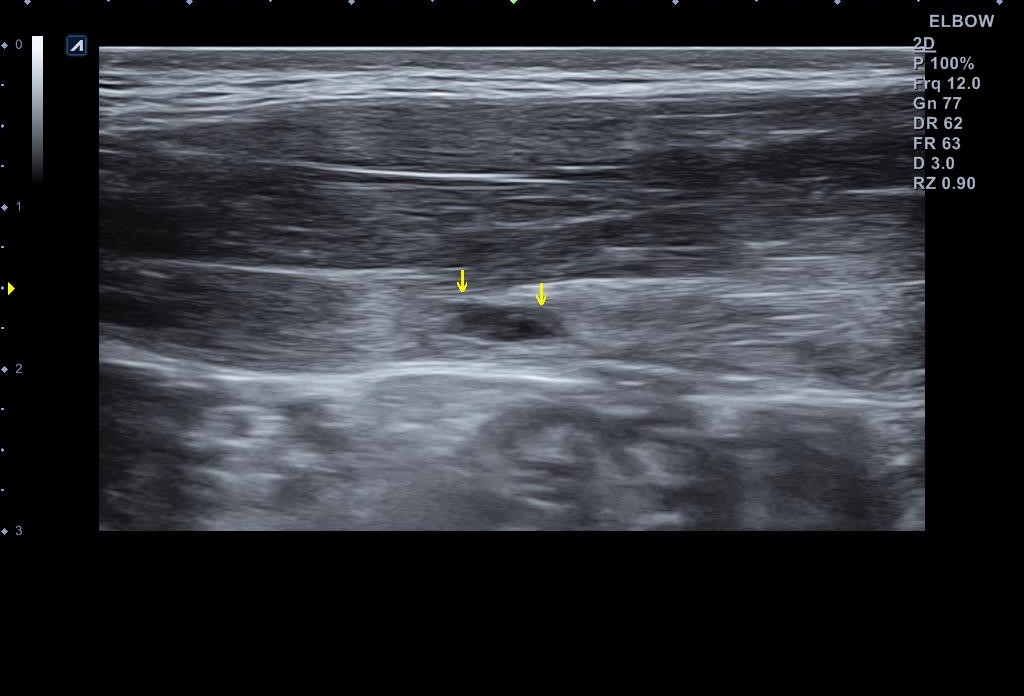

x-ray 검사와 초음파 검사를 진행했습니다. x-ray 검사는 특별한 소견이 없었구요, 초음파 검사는...

나 : 복직근 파열이 맞네요.

나 : 근육이 많이 찢어진건 아닌데... 우선 일주일 간격으로 초음파 검사를 통해 호전여부를 확인하고 운동 복귀 시기를 결정하셔야 합니다. 그때 까지는 스매싱같은 동작은 하시면 안됩니다.